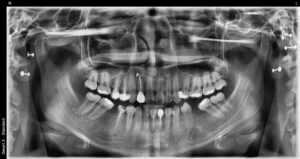

정밀한 검사를 위해

파노라마 사진을 촬영해 보았더니

해당 치아는 신경치료가 되어 있는 치아로

뿌리 끝에 염증이 있는 것을

확인할 수 있었는데요.

재 신경치료가 가능한지를

파악하기 위해 양산수면치과

에이디중부치과에서는 3D CT 촬영을 통해

정밀한 검사를 진행하였으며,

그 결과 해당 치아를 발치하지 않고

재 신경치료를 통해

한 번 더 살려 쓰는 방향으로

치료를 도와드리기로

치료 계획을 수립하였습니다.